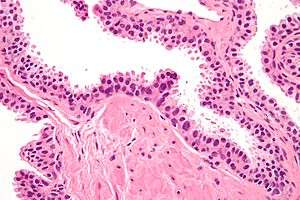

| Micrograph showing high-grade prostatic intraepithelial neoplasia. H&E stain. | |

In urologic pathology, high-grade prostatic intraepithelial neoplasia, abbreviated HGPIN, is an abnormality of prostatic glands and believed to precede the development of prostate adenocarcinoma (the most common form of prostate cancer).[1][2]

It may be referred to simply as prostatic intraepithelial neoplasia (abbreviated as PIN). It is considered to be a pre-malignancy, or carcinoma in situ, of the prostatic glands.

Microscopically, PIN is a collection of irregular, atypical epithelial cells. The architecture of the glands and ducts remains normal. The epithelial cells proliferate and crowding results in a pseudo-multilayer appearance. They remain fully contained within a prostate acinus (the berry-shaped termination of a gland, where the secretion is produced) or duct. The latter can be demonstrated with special staining techniques (immunohistochemistry for cytokeratins) to identify the basal cells forming the supporting layer of the acinus. In prostate cancer, the abnormal cells spread beyond the boundaries of the acinus and form clusters without basal cells. In HGPIN, the basal cell layer is disrupted but present. PIN is primarily found in the peripheral zone of the prostate (75-80%), rarely in the transition zone (10-15%) and very rarely in the central zone (5%), a distribution that parallels the zonal distribution for prostate carcinoma.[4]